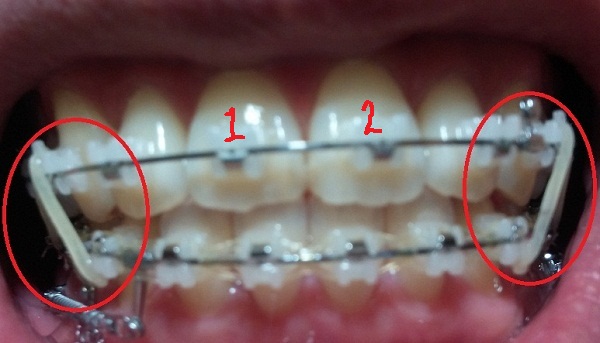

[스프링 정면]

+스프링사이에 또 다른 쇠기둥 보이시죠?! 저건 스프링이 잇몸에 닿아서 짓눌리지 않게 하기 위해서 해둔 조치랍니다.(제가 눌려서 아프다고 호소했더니 저런 방법으로 해주셨어용^^)